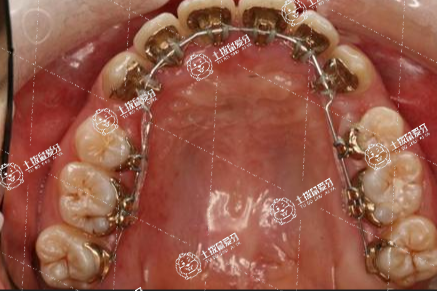

牙齒矯正難度需根據(jù)患者牙齒癥狀的嚴(yán)重程度區(qū)分。較為簡(jiǎn)單牙齒矯正,患者主要表現(xiàn)僅僅是輕中度的擁擠;稍難一些的矯正則由于患者存在下頜的嚴(yán)重?fù)頂D,以及嚴(yán)重深覆合,或者前牙開(kāi)于頜。困難的牙齒矯正,多由于主患者為重度的擁擠,且可伴隨骨性因素,各個(gè)平面均表現(xiàn)為不調(diào),并伴有嚴(yán)重的齲齒、大小牙的情況。

牙齒有一點(diǎn)不齊,矯正難度大,患者可以通過(guò)配戴矯治器、拔除牙齒、修復(fù)等手段糾正牙齒不齊。一般患者牙齒有一點(diǎn)不齊,矯正難度大可能與牙齒擁擠、牙周炎、齲齒、先天性牙齒缺失等因素有關(guān),建議及時(shí)就醫(yī),在醫(yī)生的指導(dǎo)下進(jìn)行矯正。

患者牙齒有一點(diǎn)不齊,矯正難度大,還與錯(cuò)頜畸形、拔牙等因素有關(guān)?;颊邞?yīng)及時(shí)就醫(yī),在醫(yī)生的指導(dǎo)下進(jìn)行治療。同時(shí)患者在配戴矯治器期間,要注意口腔衛(wèi)生,不要吃生冷、辛辣、油膩的食物,以免出現(xiàn)矯正效果不佳的情況。